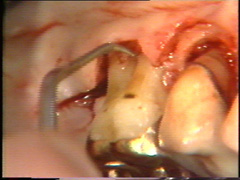

Se realiza una

segunda insición horizontal en el fondo de la bolsa para facilitar el levantamiento del tejido de

granulación

El levantamiento del tejido de

granulación se realiza en un tiempo y el procedimiento en sí es

exigente. Puede hacerse antes o después del levantamiento del colgajo.

El sangrado se controla bien y el tiempo de exposición del hueso

al medio bucal es reducido, cuando el tejido de granulación es

eliminado antes del levantamiento del colgajo.

Observese como se

ha eliminado el tejido de granulación en el segundo premolar. |

Eliminación del

tejido de granulación |

Las superficies de la raíz se limpian

(raspado y alisado radicular) cuidadosamente y el tejido de granulación en los

defectos óseos (cráter) es eliminado. En la superficie bucal del segundo premolar hay

un cráter óseo y cálculo en la supericies dental adyacente.

El cálculo del segundo premolar

está unido firmemente a la superficie dental y es un proceso tedioso el

quitarlo.